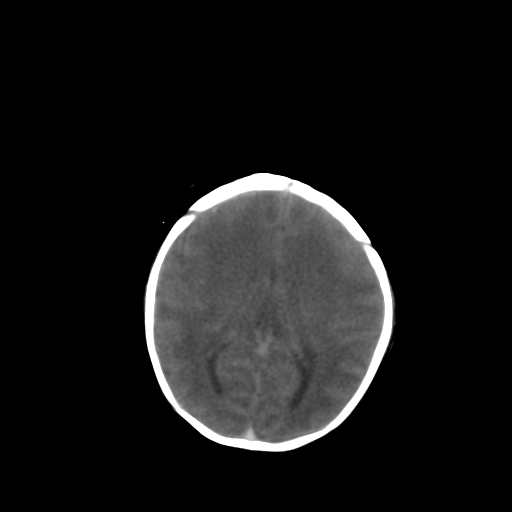

男,2天,孕31周早产儿,出生后窒息3分钟,精神反应差。

脑实质弥漫低密度,灰白质界限不清:结合临床考虑重度hie